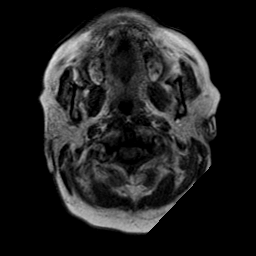

Cerebral hemorrhage, MR Study mr-t1 -- Slice #1

[Home][Help][Clinical] Slice 1